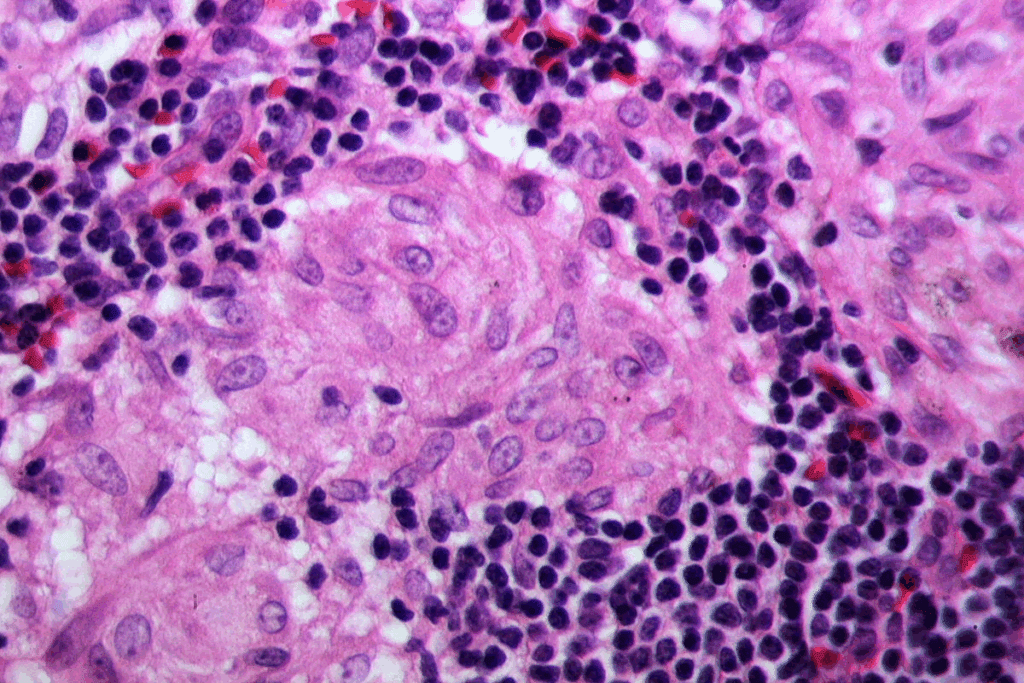

Scarlet fever is a bacterial infection that causes dark red spots on the tongue and sore throat. It is caused by Group A Streptococcus bacteria. This infection leads to a strawberry tongue appearance.

Group A Streptococcus Infection Process

The infection starts when Group A Streptococcus bacteria colonize the throat. They produce toxins that cause symptoms of scarlet fever. This bacterial infection is highly contagious and can spread through direct contact with an infected person’s respiratory secretions. Knowing how it spreads helps in diagnosing and treating scarlet fever.

Characteristic Tongue Appearance

The strawberry tongue is a key sign of scarlet fever. This tongue appearance is due to enlarged papillae on the tongue’s surface, making it red and bumpy. The tongue starts with a white coating but turns red and swollen, like a strawberry. This symptom is a major indicator of scarlet fever.

Accompanying Throat Symptoms

People with scarlet fever often have a sore throat. The throat may look red and swollen, with white patches or pus on the tonsils. They may also have fever, headache, and swollen lymph nodes in the neck. These symptoms are important for a full diagnosis.